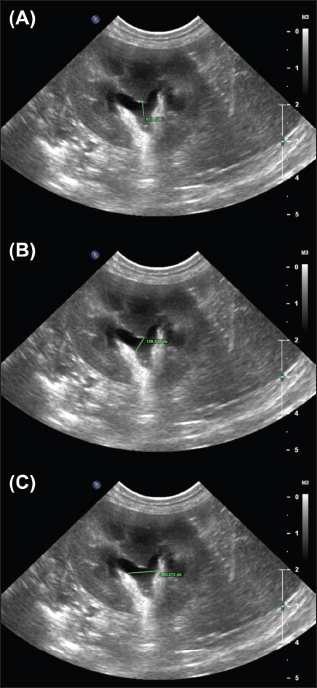

Overall, measurements from the sagittal plane performed worse than those from the dorsal and transverse planes, possibly due to the variable appearance of the renal pelvis in this plane; its margins may undulate, and it might be bisected by the renal crest depending on the level of insonation (Fig. 3). A study of murine kidneys proposed a hydronephrosis grading method that might mitigate the effects of this variation by calculating the percentage of renal height comprised of renal parenchyma (as opposed to renal pelvis) in the sagittal plane (Carpenter et al., 2012). Disappointingly, the interobserver variability of this method was found to be only ‘Moderate’ when applied to cats in our study (Fig. 4).

Fig. 4. Examples of the “SPP” measurement, adapted from methods proposed in murine kidneys by Carpenter et al., (2012). The longitudinal renal length is measured as a guideline (i). Perpendicular to this, the transverse renal width (ii), renal pelvis diameter (iii), and renal papilla width (iv) are measured, and the percentage of the renal height that is comprised of renal parenchyma (as opposed to pelvis) is calculated. Note that the renal papilla is not visible in (b), which would result in a lower overall percentage of renal parenchyma contributing to renal height in this image.

Supplementary 4. Examples of the ‟Dorsal crest-to-ureter” (DCU) (A) and ‟Dorsal pelvic width (DPW)” (B) measurements performed by observers.